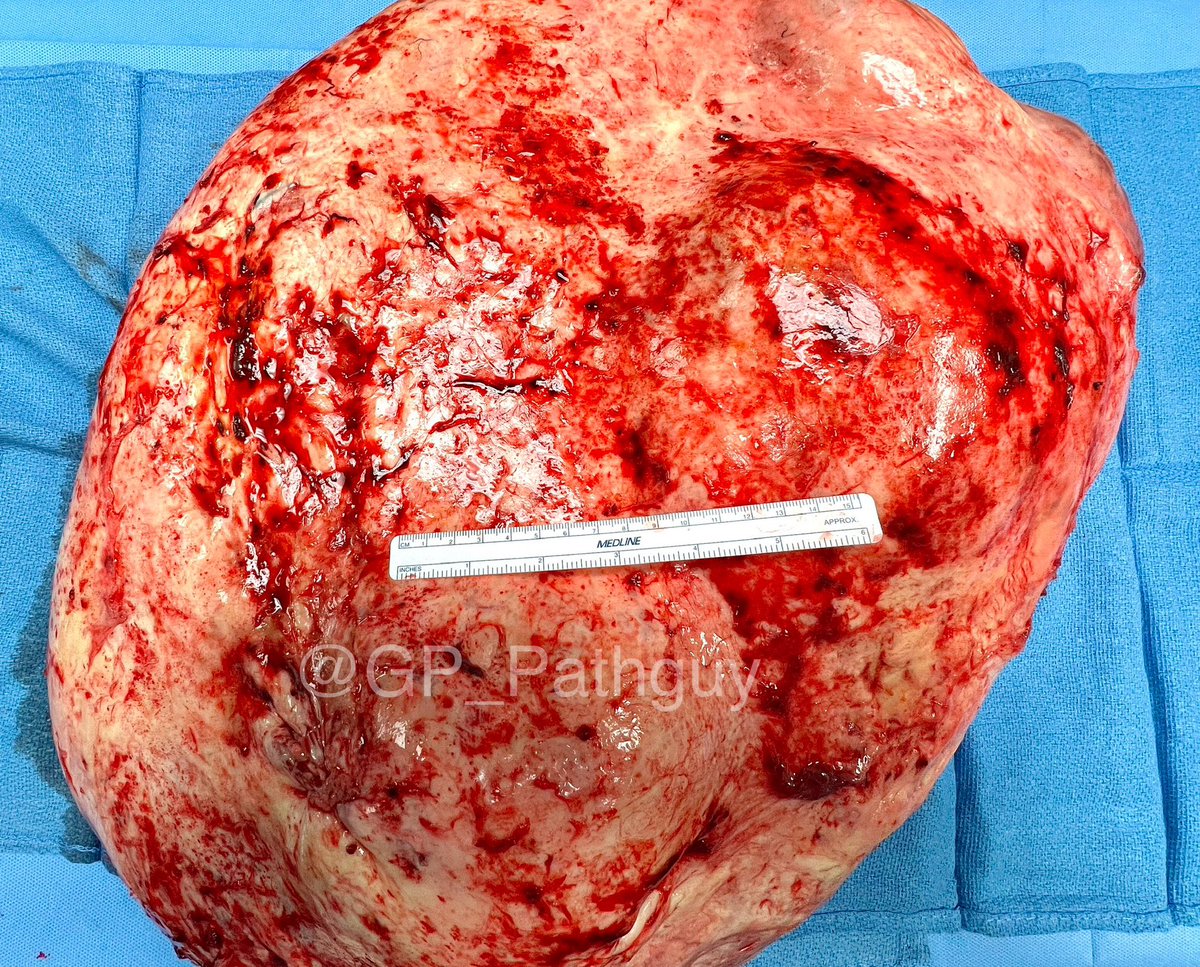

Schistosoma haematobium in a high-grade urothelial carcinoma resection. Weirdly present in the ureters and seminiferous tubules as well. Critters are among us. @UTHSC_ID @natesumMRSA